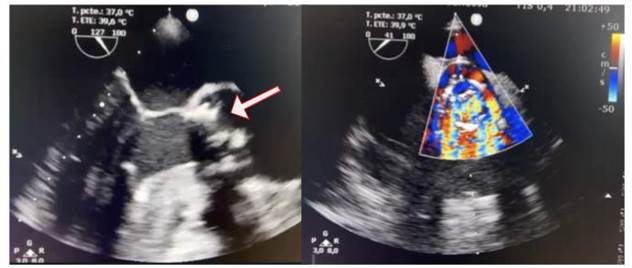

Se realiza un ecocardiograma transtorácico Doppler color, en el que se observa hipertrofia excéntrica del ventrículo izquierdo, función sistólica conservada, bioprótesis en posición aórtica estable, se registra una insuficiencia central con un tiempo de hemipresión (PHT) de 150 ms. Se produce un engrosamiento valvular con imagen móvil adherida a esta, con aumento de los gradientes 78/38 mmHg. Posteriormente, se realiza un ecocardiograma transesofágico Doppler color (Figura 3), que evidenció prótesis biológica en posición aórtica disfuncionante, con múltiples vegetaciones adheridas, la más grande de 8 mm por 5 mm, lo que genera destrucción del aparato valvular e insuficiencia severa (PHT 150 ms).

Figura 3 Ecocardiograma basal A. Transesofágico a 120 grados, se observan múltiples vegetaciones adheridas a bioprótesis aórtica, la más grande 8 mm por 5 mm (flecha). B. Doppler color a 45 grados, se observa jet de insuficiencia aórtica severa.